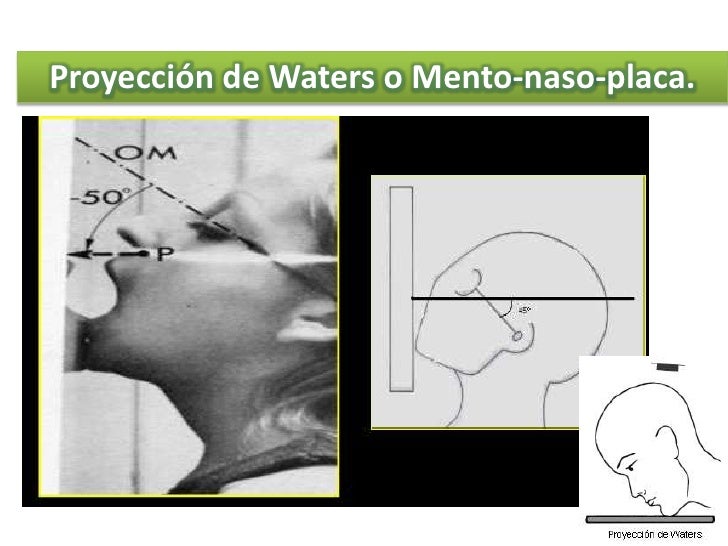

Download scientific diagram | Proyección de Waters: aumento de densidad de partes blandas de los senos maxilares (estrella) y presencia de masa en la faringe (flecha). from publication: Pólipo.. Citation, DOI, disclosures and article data. The Caldwell view is a caudally angled radiograph, with its posteroanterior projection allowing for minimal radiation to the orbits. This view may be used in imaging of the skull or facial bones depending on the clinical indications.

Dx por imagen Craneo Columna RADIOGRAFIA DE CRANEO Proyección de Waters, esta proyección nos

Waters de Cráneo Orthodiagnóstico

ESTUDIO RX 4 Proyeccion de Waters YouTube